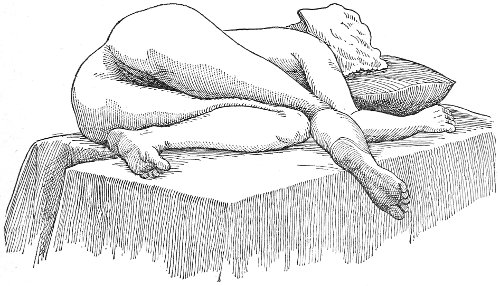

The Sims speculum enables us to make the most thorough inspection of the vagina, the vaginal vault, and the vaginal cervix. The Sims speculum is merely a hook or retractor for the perineum, and may be introduced with the woman in the dorsal position, the Sims position, or the genu-pectoral position. If the Sims speculum is introduced in the dorso-sacral position, it is necessary to hold forward the anterior vaginal wall in order to obtain a view of the cervix.

Fig. 10.—The Sims position.

The Sims position, which is also called the latero-abdominal position, is shown in Fig. 10. The woman is placed on the bed or table upon her left side. The side of the face is upon the pillow; the left arm is behind the back, so that the left breast rests upon the table. The thighs are flexed upon the abdomen at an angle of about 90° to the trunk. The right thigh is more flexed than the left, so that the right knee may touch the table above the left knee. The legs are flexed on the thighs. In this position there is a tendency for the intestines, following the force of gravity, to fall from the pelvis, 32 and for the uterus and other pelvic viscera to be drawn up. When the perineum is retracted with the blade of the Sims speculum, air will enter the vagina and the vaginal slit will become distended (Fig. 11). To facilitate inspection of the cervix it is usually necessary also to push forward the anterior abdominal wall by some kind of depressor, such as the one shown in Fig. 8.